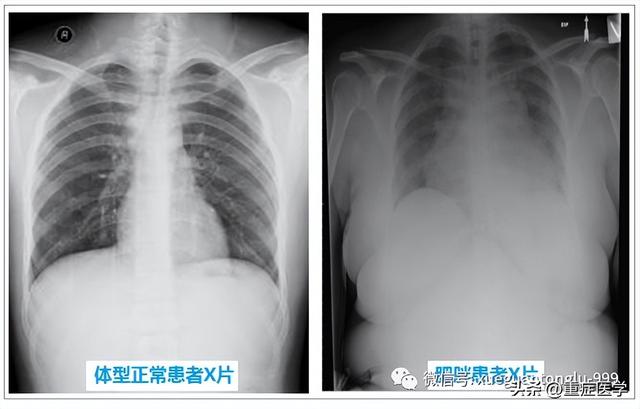

建议术前胸片检查,以明确有无异常情况:比如右位心往往合并先天性血管畸形,置管时需要慎重思考,比如肥胖患者或者因为其他原因膈肌上抬患者的标准第3肋间所对应的位置不是上腔静脉与右心房交界处。